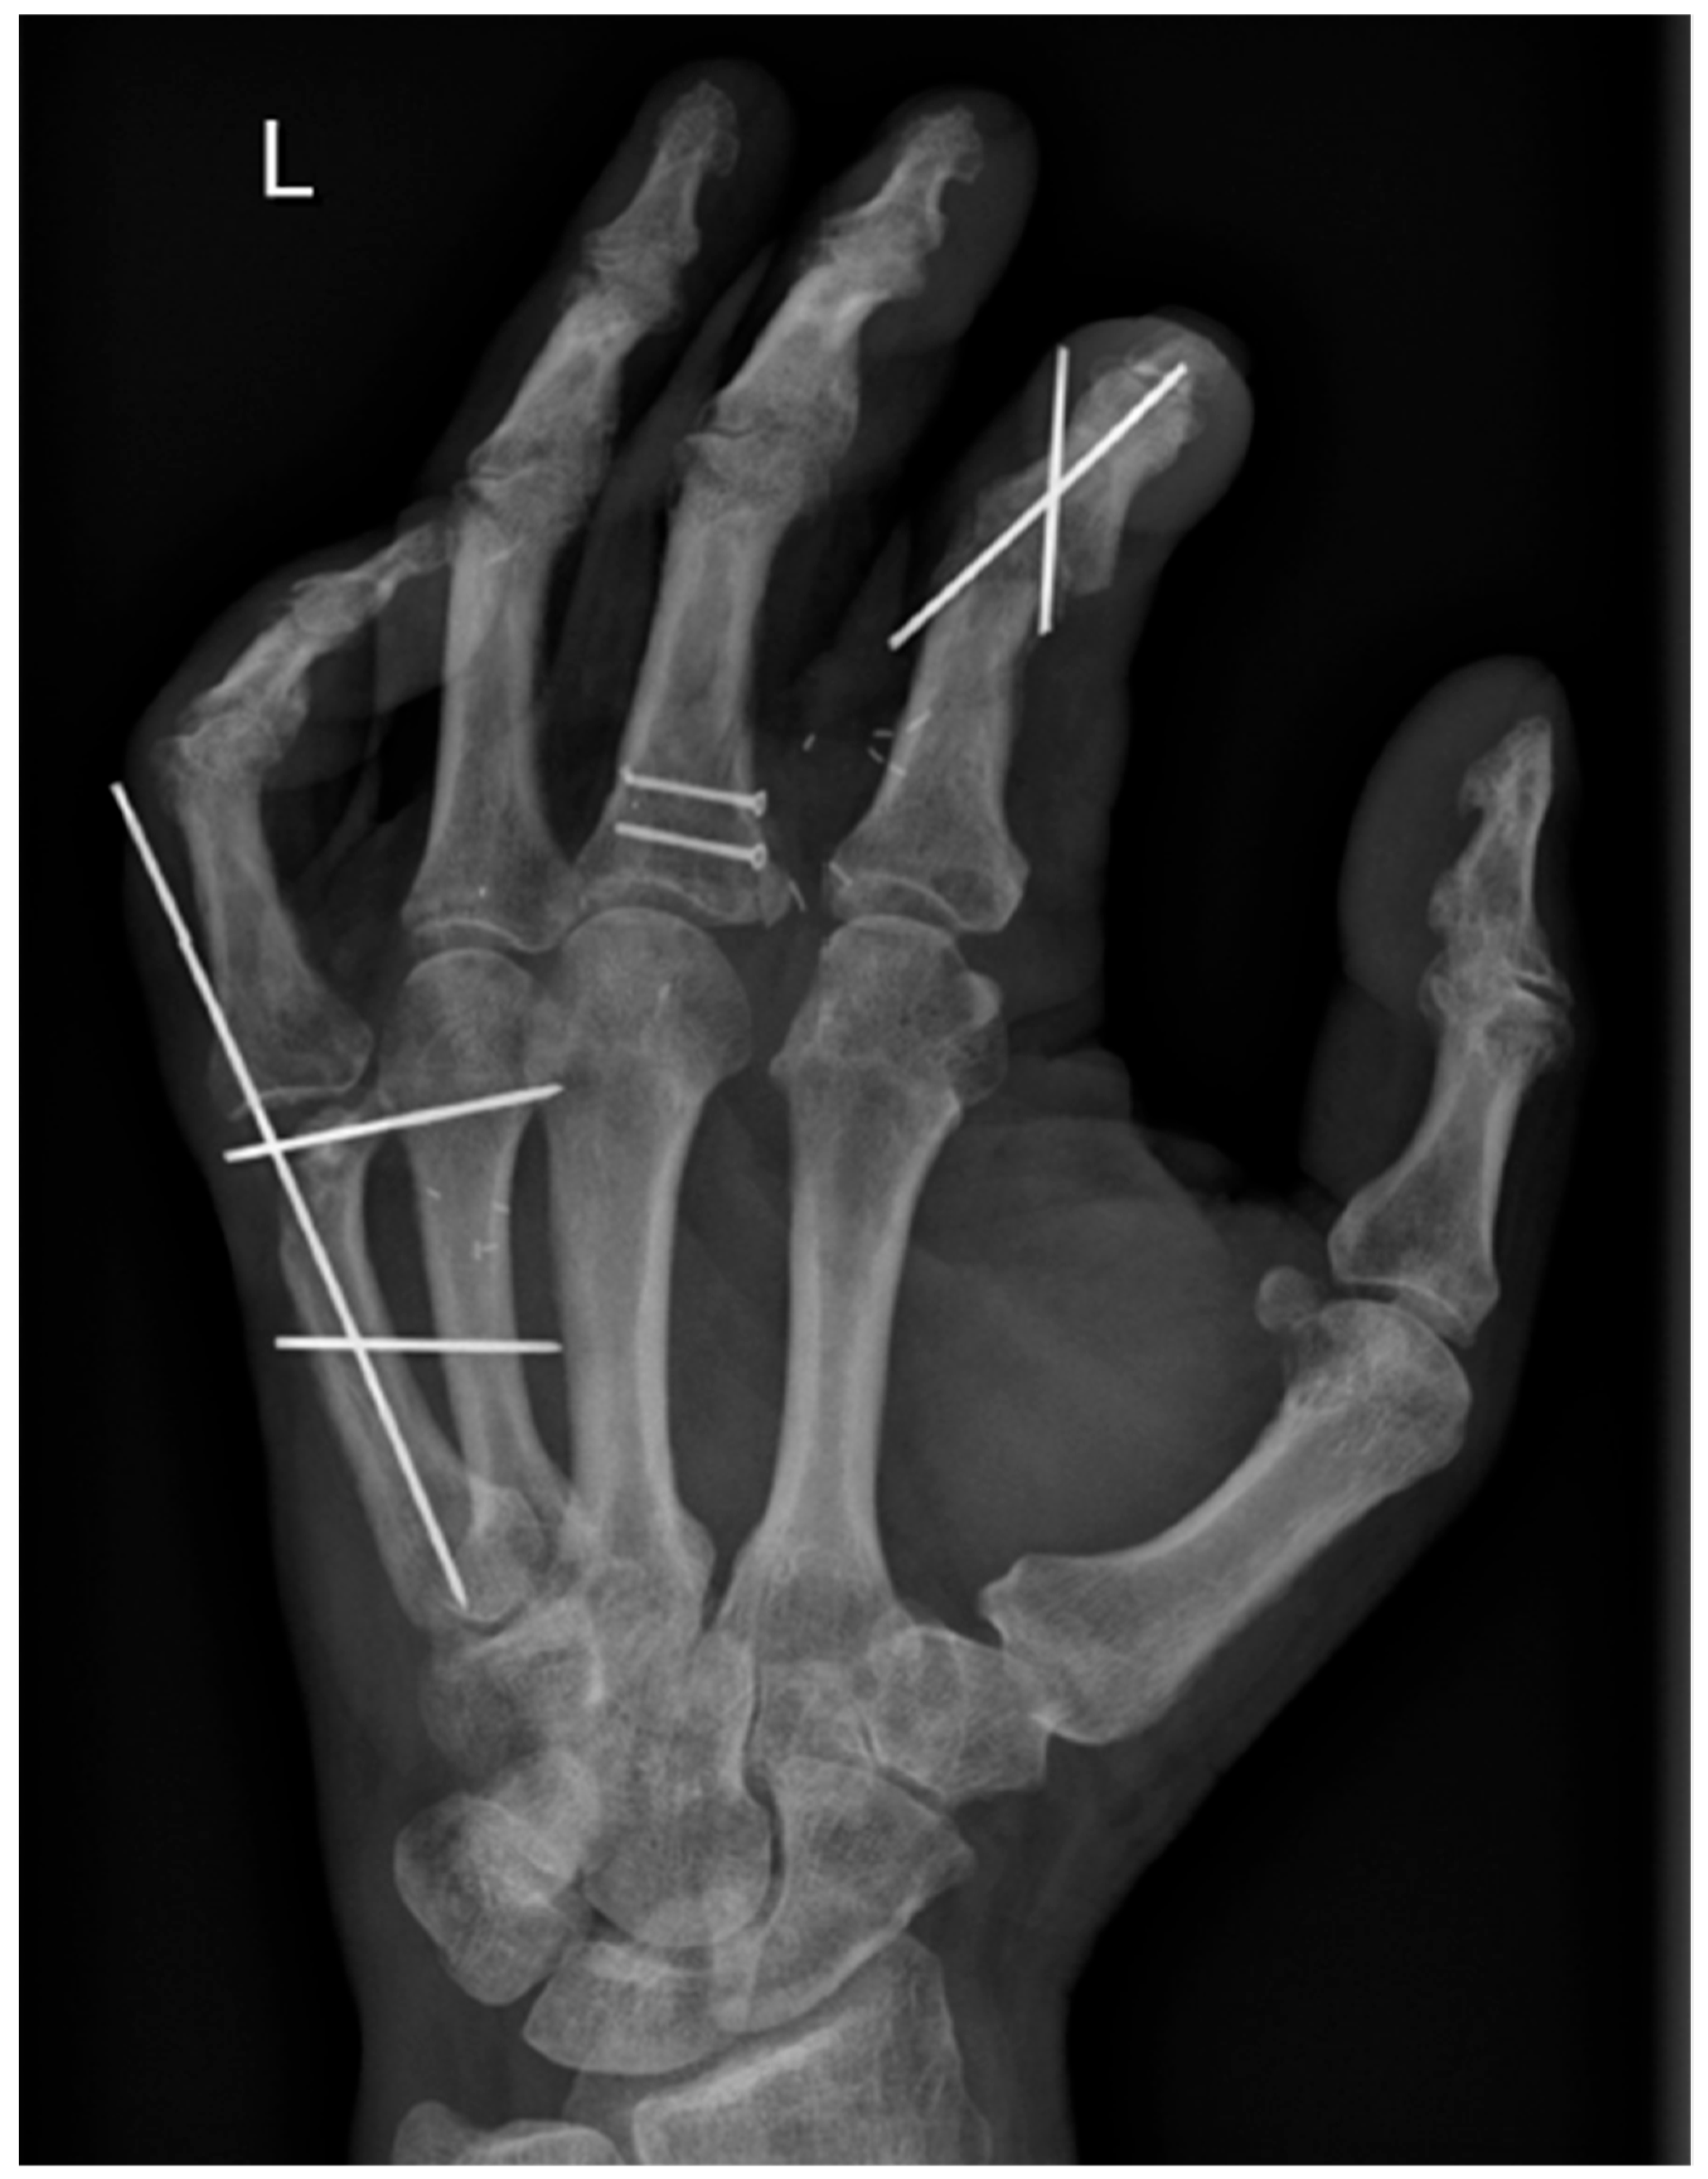

2. Case Report